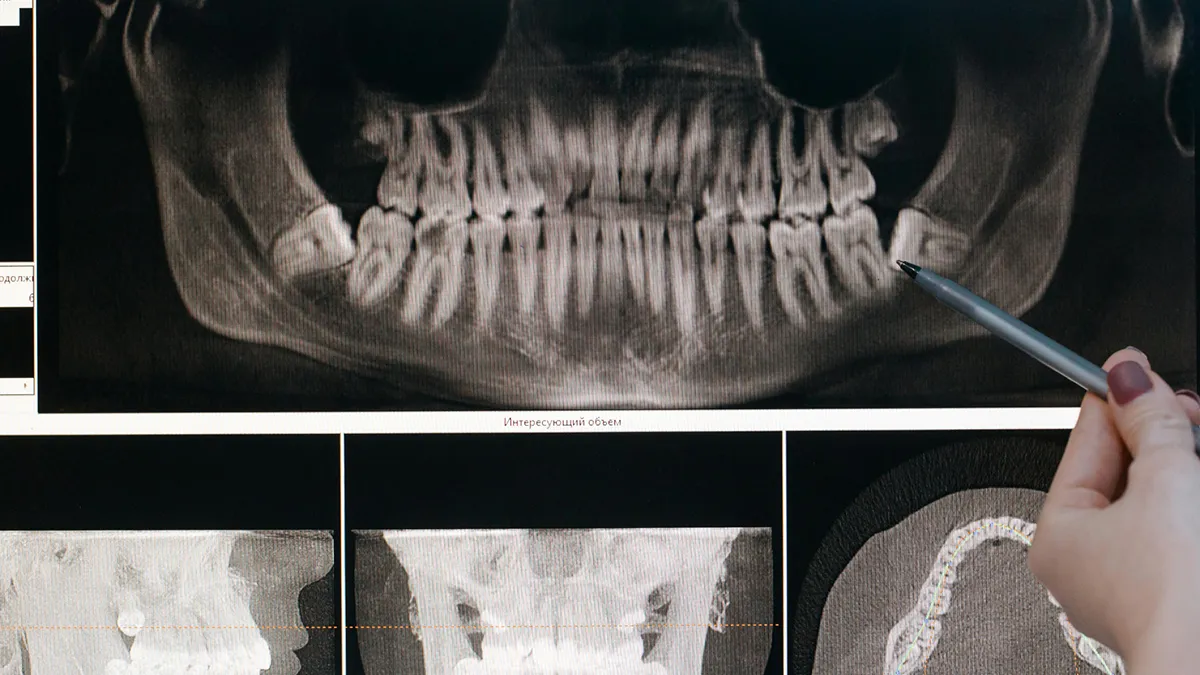

Nei nostri studi dentistici utilizziamo solo le più moderne tecnologie dentali per garantire diagnosi precise e trattamenti efficaci. Le nostre attrezzature all’avanguardia ci permettono di svolgere interventi minimamente invasivi, riducendo i tempi di recupero e migliorando l’esperienza complessiva del paziente.

Implantologia a carico immediato a Brescia

Per chi ha perso uno o più denti e vuole tornare a sorridere senza compromessi.

L’implantologia a carico immediato è una tecnica avanzata che consente di inserire impianti dentali e denti fissi provvisori in un’unica seduta, senza dover aspettare mesi tra l’intervento e l’applicazione della protesi.